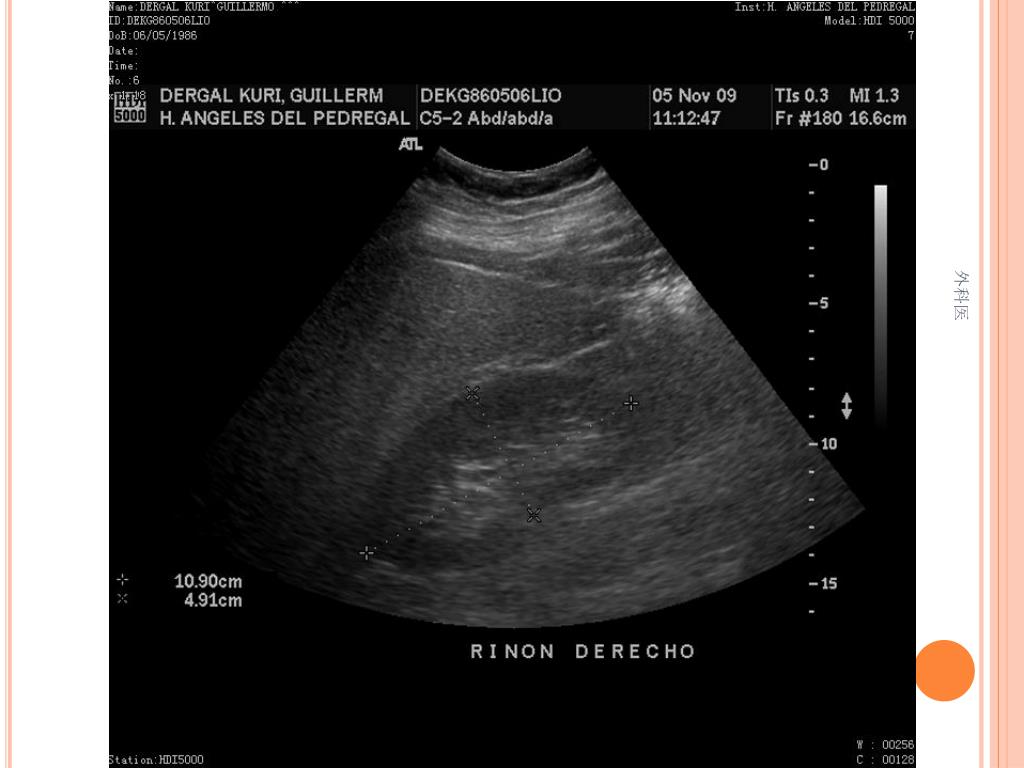

21. 外科医

44. Tips • Leucocitos Mas de 20000/ml • Mas de 20% de la apéndices no se llenan con el bario por enema. • USG sensibilidad del 85% y Especificidad de mas 90% para Apendicitis Aguda. • TAC de Abdomen cortes de 5mm, sensibilidad y especificidad del 90% para dolor abdominal. • Analisis de 75000, taza de apendice negativa de 6% Hombres y 13% Mujeres 外科医